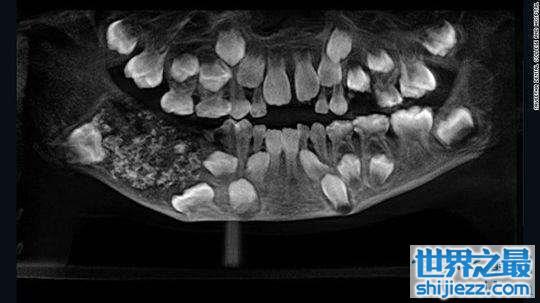

印度7岁男孩下颚肿胀,嘴里竟然多长了526颗牙齿

一名七岁的印度男孩在爸爸妈妈的陪同下前往金奈南部的牙科医学院。据报道,他自三岁起就向爸爸妈妈抱怨过下巴肿胀不适,当时爸爸妈妈曾带他去过另一家医院。但由于年岁太小,医生为他检查时,他不肯合作。但是,跟着疼痛和肿胀日益加剧,爸爸妈妈决定再次送他就医。

光片显示情况异常,医生决定为他做进一步的检查。手术发现,这名男孩的下颚上有一个明显的袋状肿块,里边包含526颗牙齿。